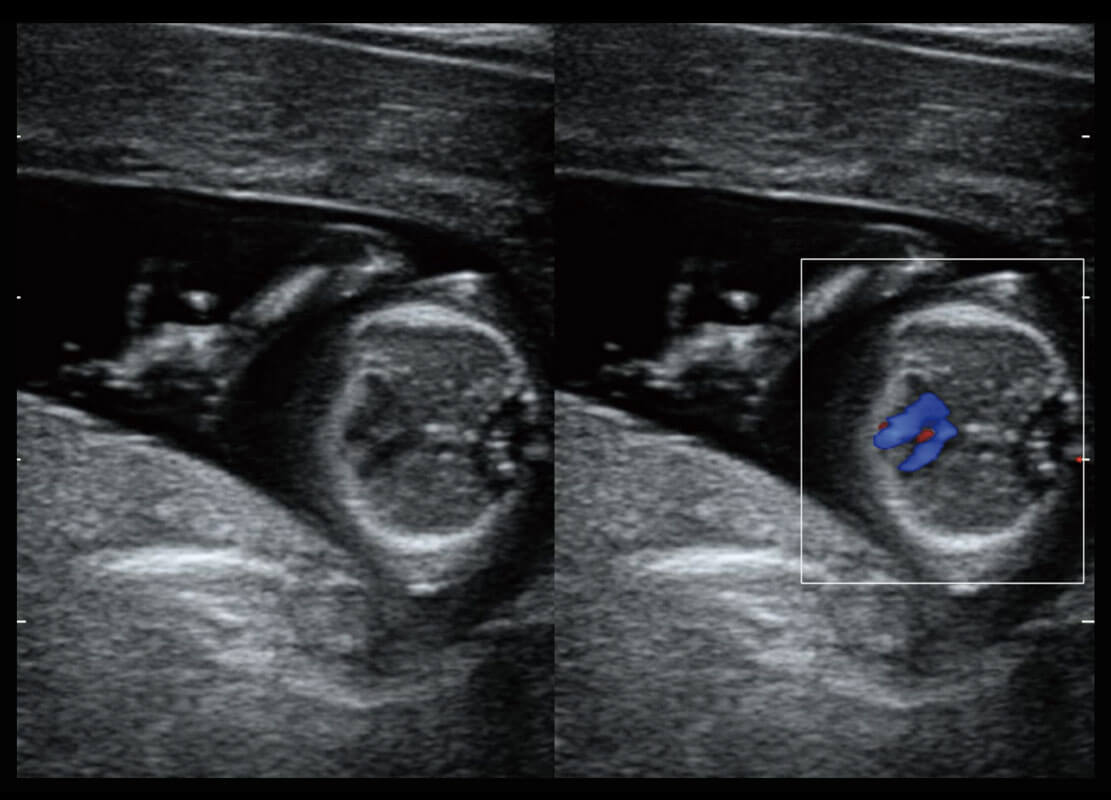

P60搭载宽频带线阵探头、宽景成像、弹性成像技术,为您提供乳腺应用方案。P60支持高频相控阵探头、线阵探头、腹部高频探头、腹部微凸探头等,丰富的探头群搭载敏感的彩色血流成像,适用于新生儿多种脏器检测要求,满足新生儿筛查需求。

新生儿肝血管癌

新生儿心脏